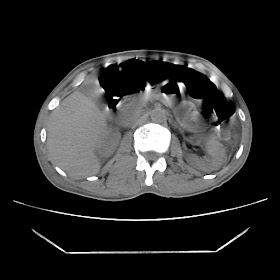

A 56 years old man with

HRCT done on summer season starting 2016